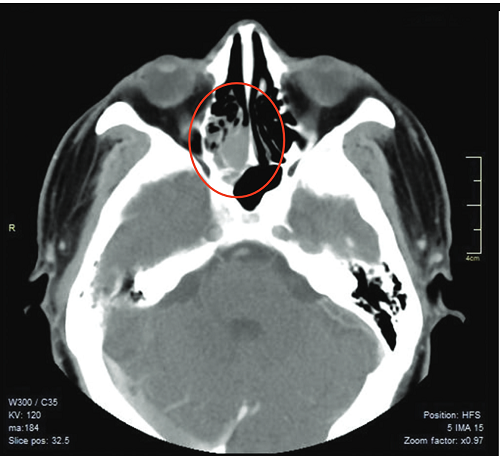

Glomangiopericytoma

A Rare Sinonasal Neoplasm

Karen Damian, Rachel Alegata

46-49